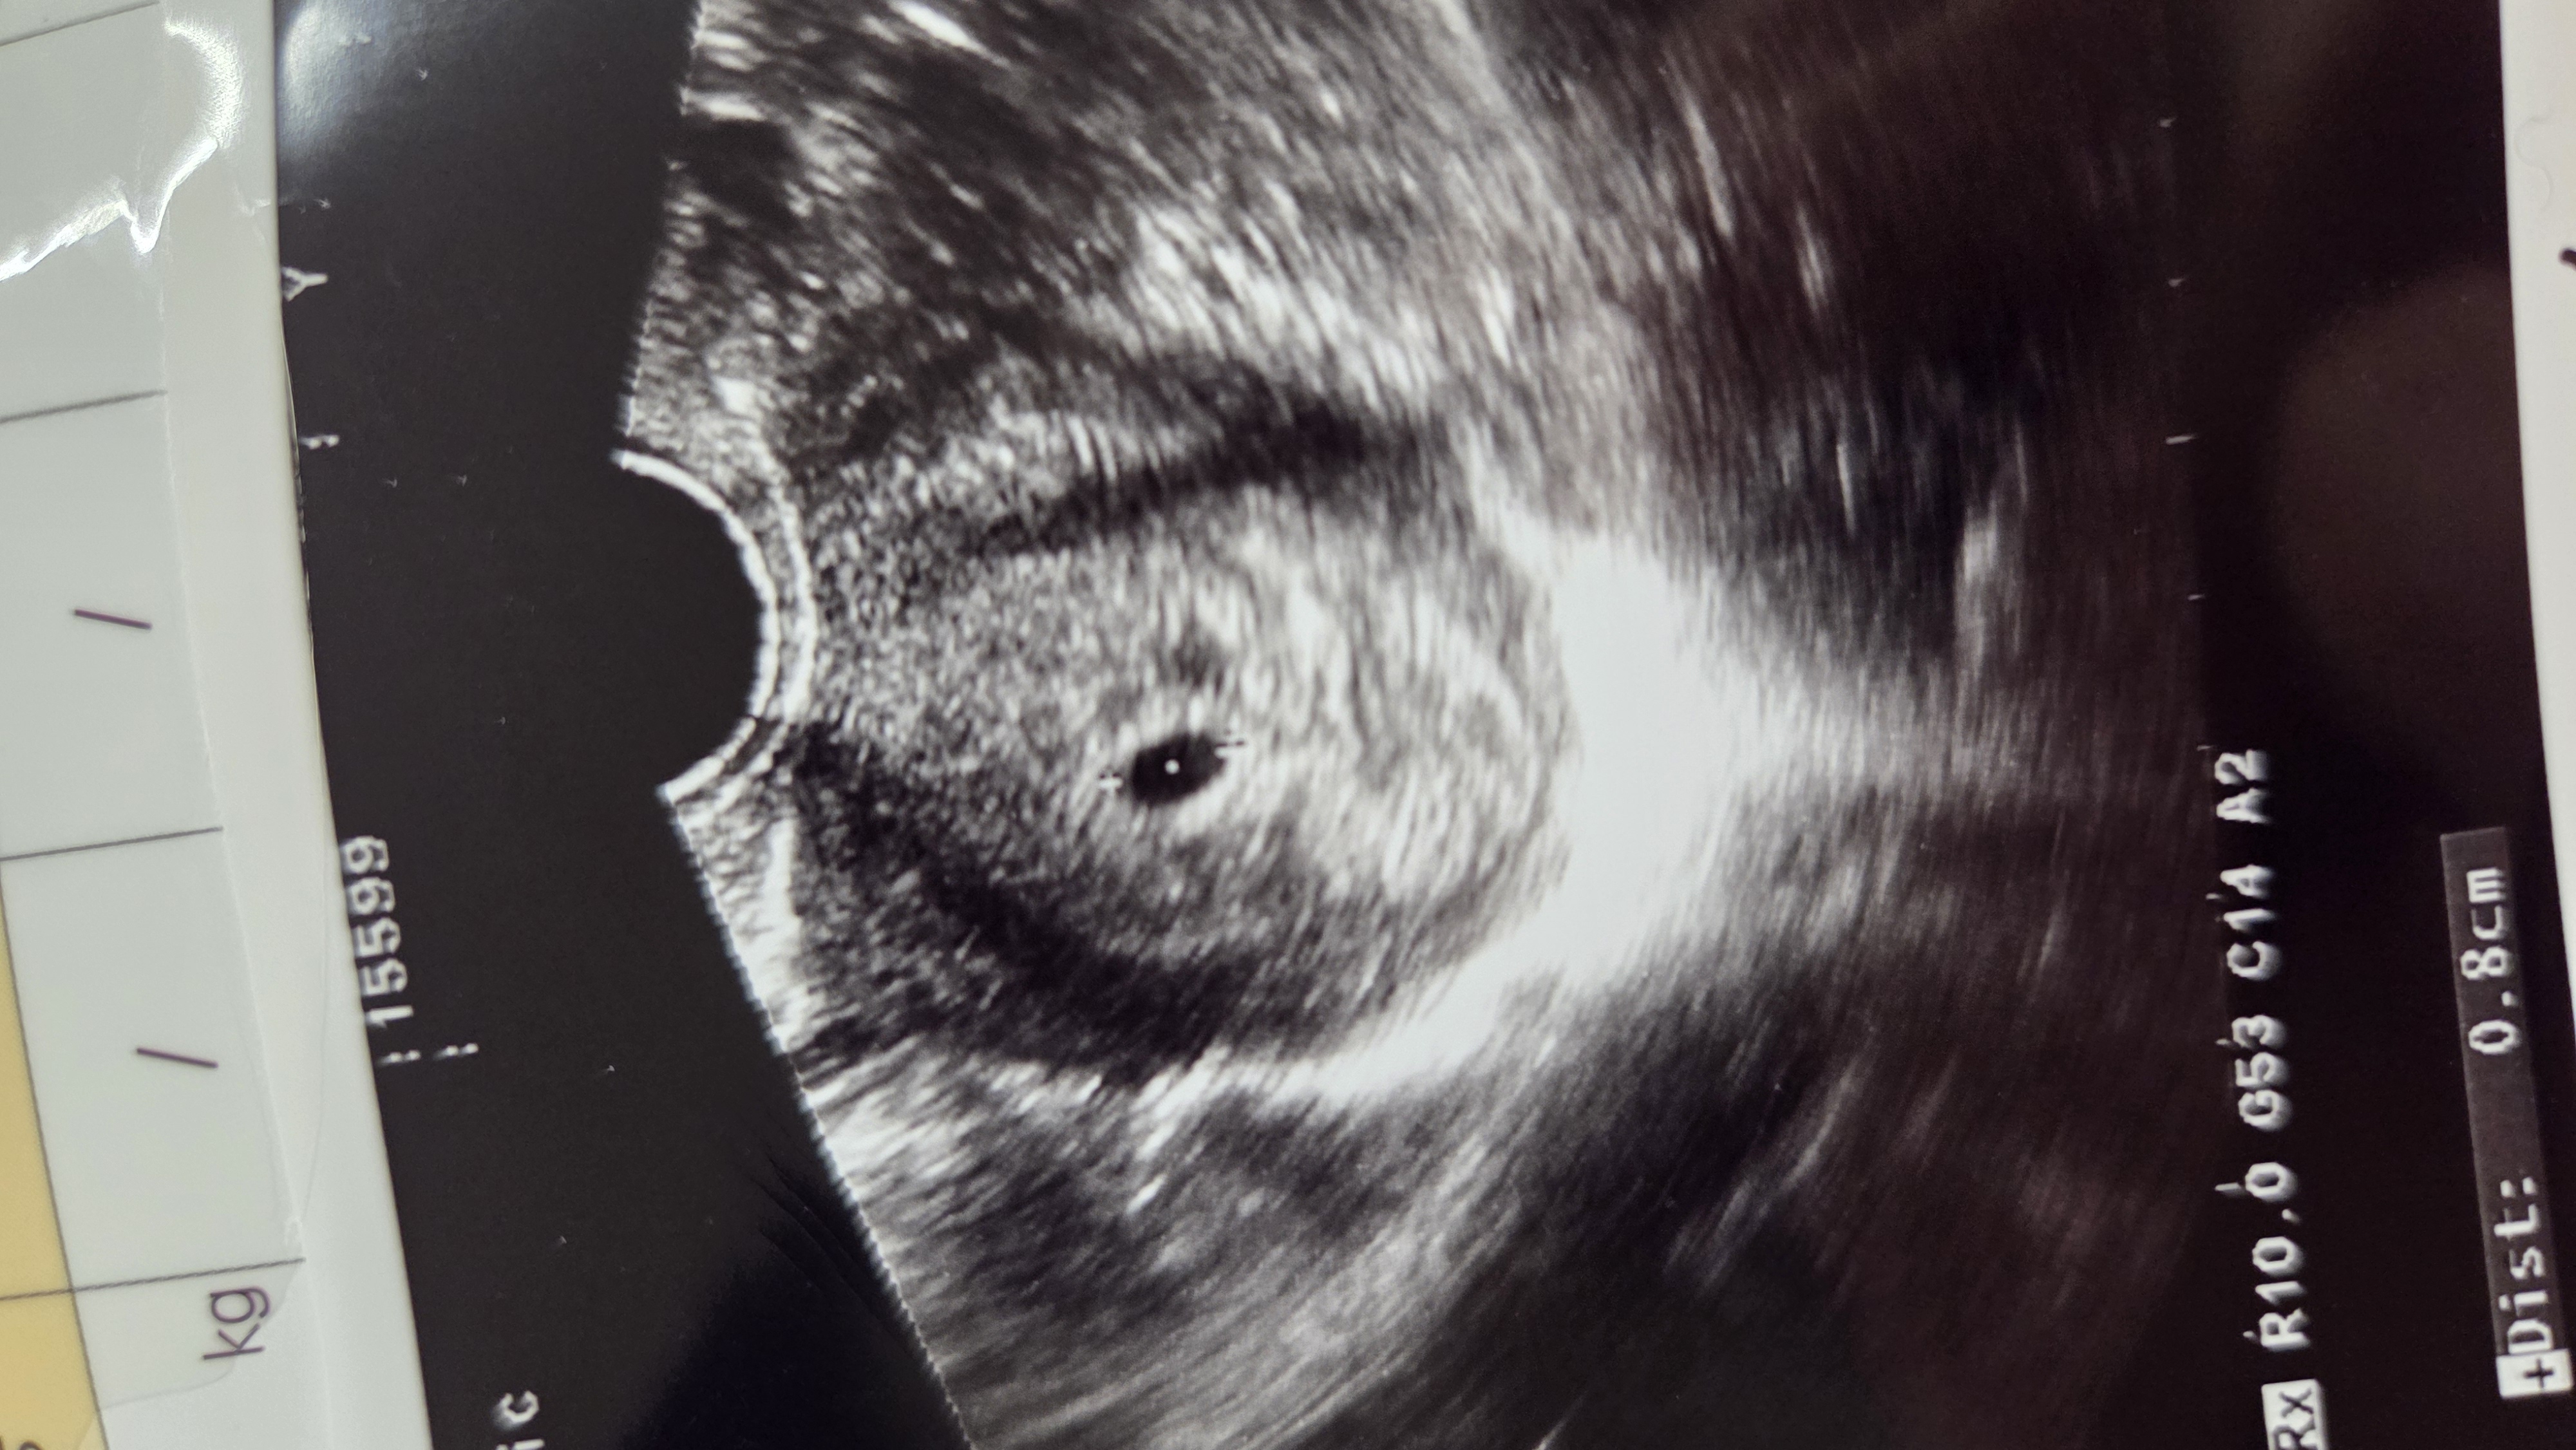

포스팅을 마무리하며 sum up을 하자면 우리 부부는

마동석 광고로 시작해서 단꿈 체험단 선정, 아기 소식까지

기대 이상으로 나비엔 숙면매트 사계절 Pro 덕분에

판타스틱한 연말을 보냈고:)